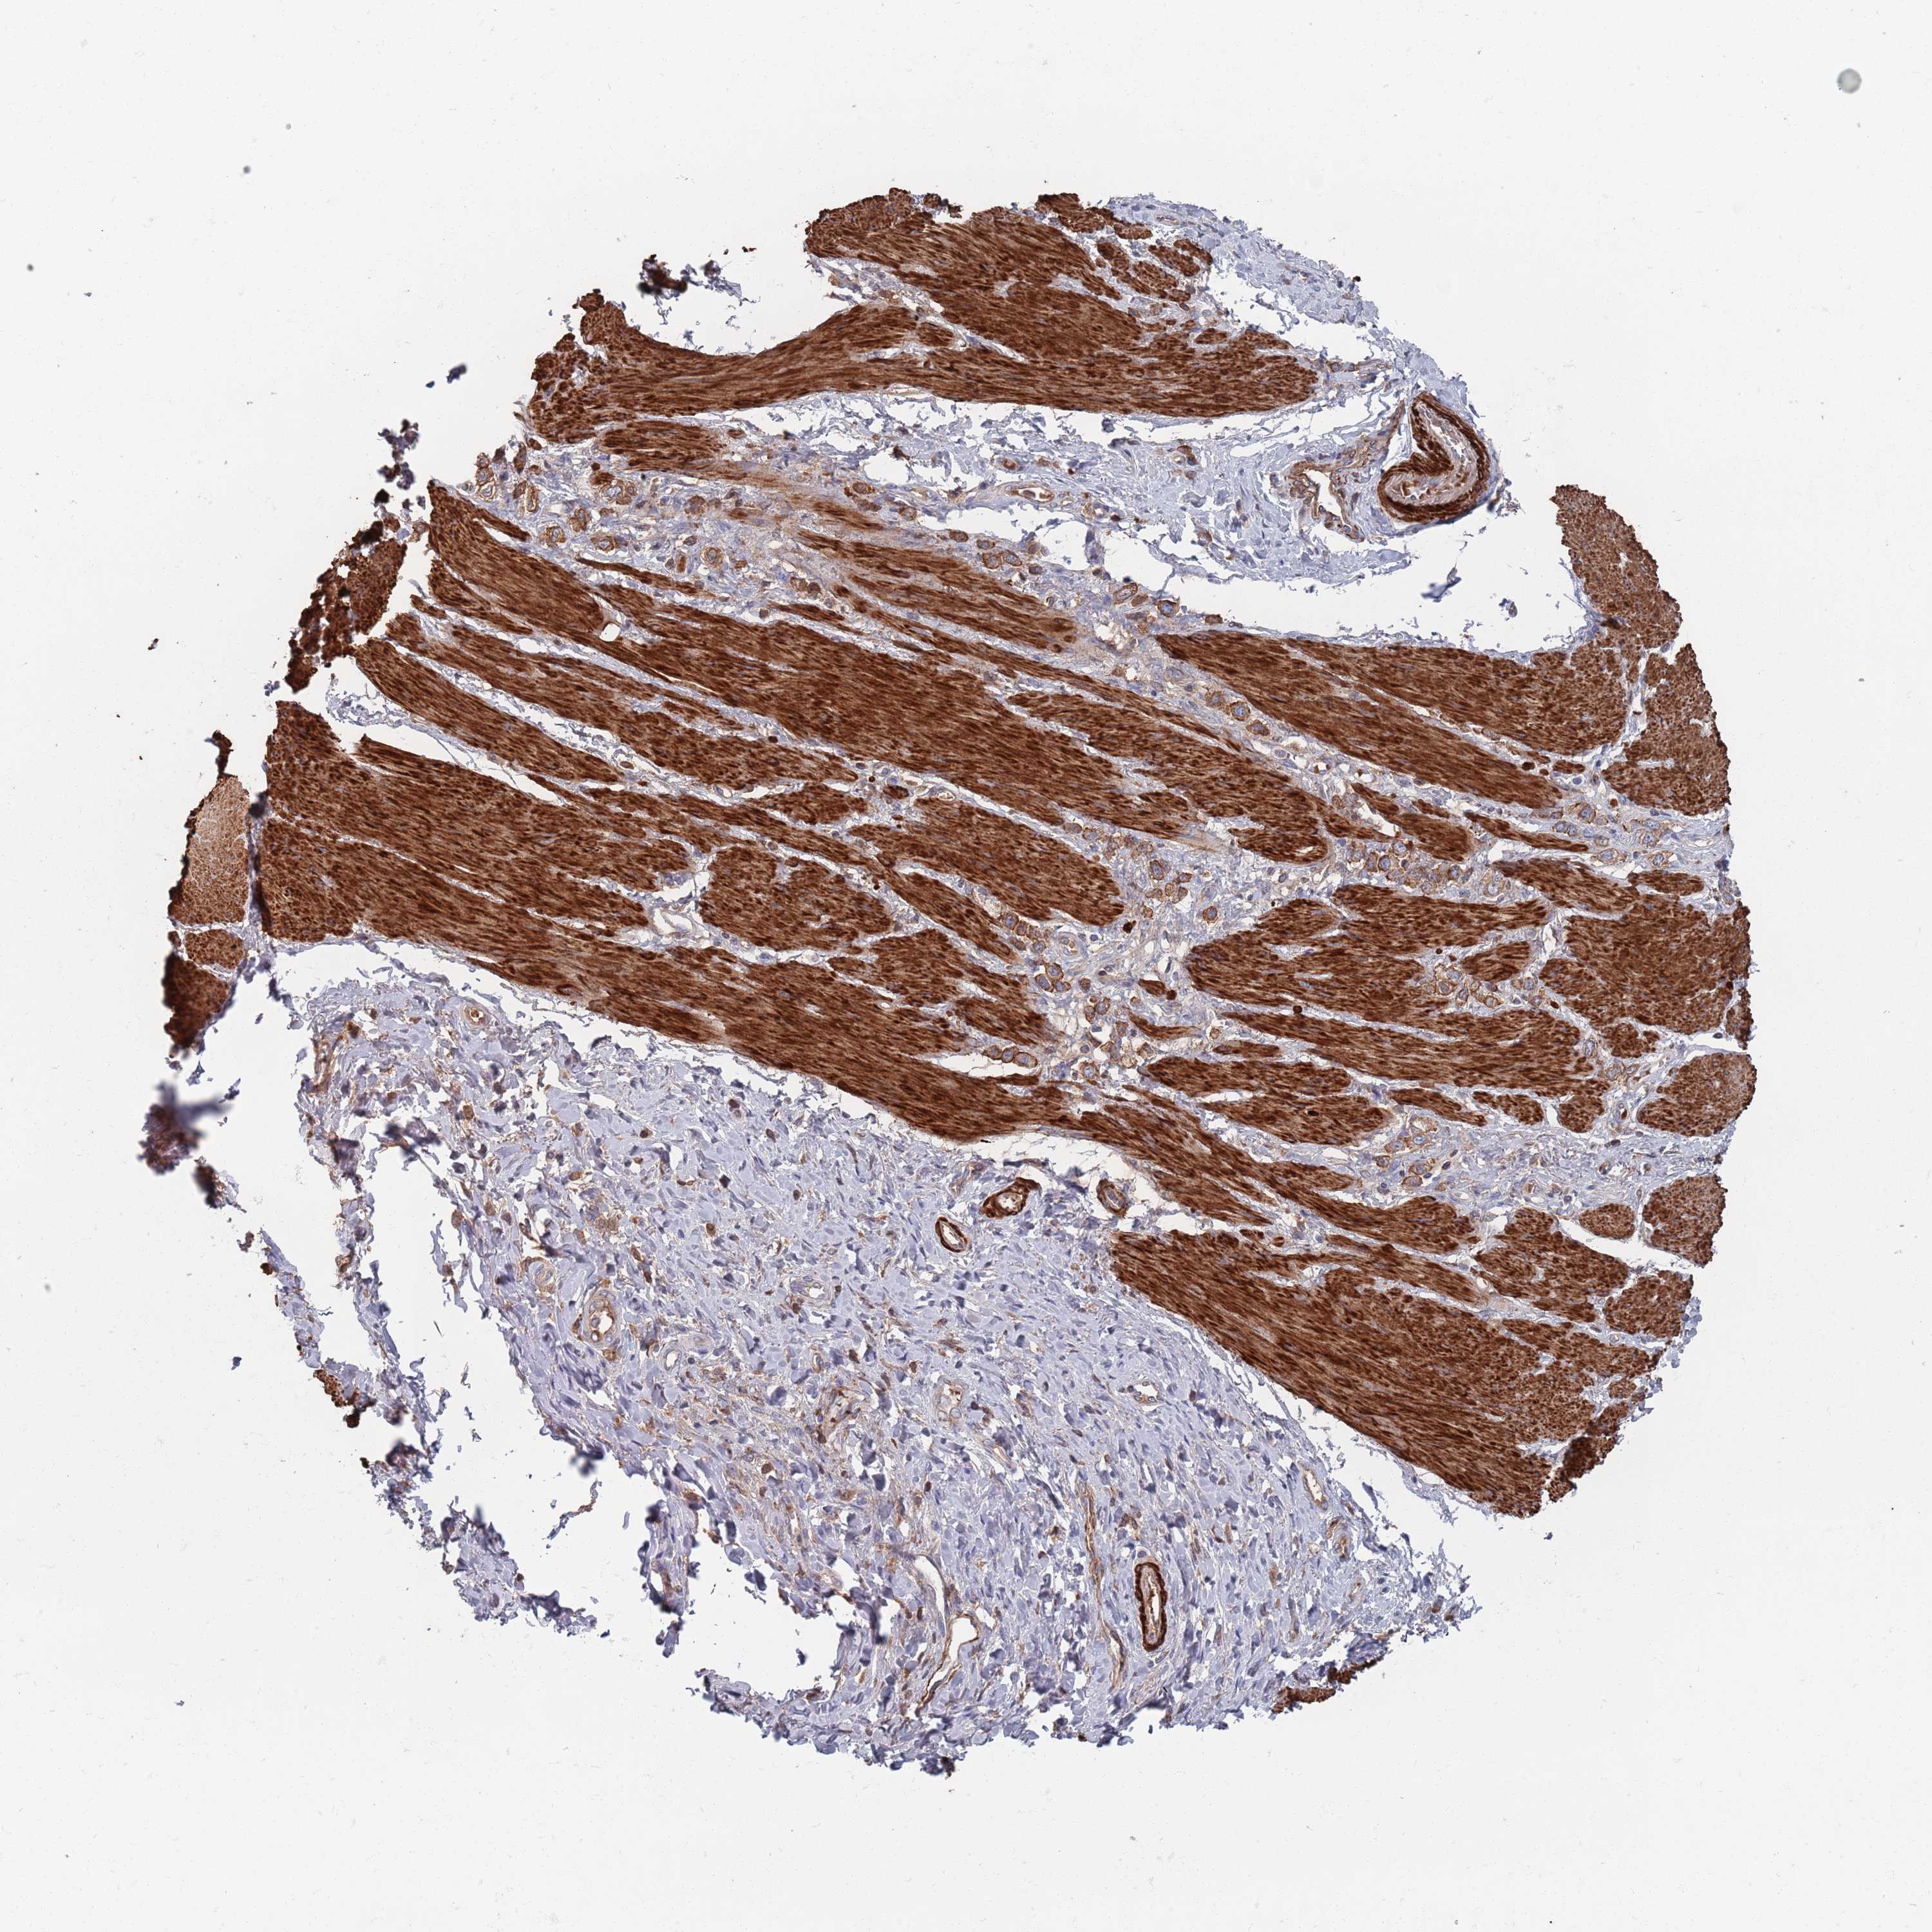

STOMACH CANCER - Protein expressioni

A mouse-over function shows sample information and annotation data. Click on an image to view it in a full screen mode. Samples can be filtered based on level of antibody staining by selecting one or several of the following categories: high, medium, low and not detected. The assay and annotation is described here.

Note that samples used for immunohistochemistry by the Human Protein Atlas do not correspond to samples in the TCGA dataset.

Antibody stainingi

Antibody staining in the annotated cell types in the current human tissue is reported as not detected, low, medium, or high, based on conventional immunohistochemistry profiling in selected tissues. This score is based on the combination of the staining intensity and fraction of stained cells.

Each image is clickable and will lead to virtual microscopy that enables deeper exploration of all samples and also displays staining intensity scores, fraction scores and subcellular localization as well as patient and tissue information for each sample.

Antibody HPA042978

Antibody HPA048473

Staining

High

Medium

Low

Not detected

Intensity

Strong

Moderate

Weak

Negative

Quantity

>75%

75%-25%

<25%

None

Location

Nuclear

Cytoplasmic/membranous

Cytoplasmic/membranous,nuclear

Adenocarcinoma, NOS